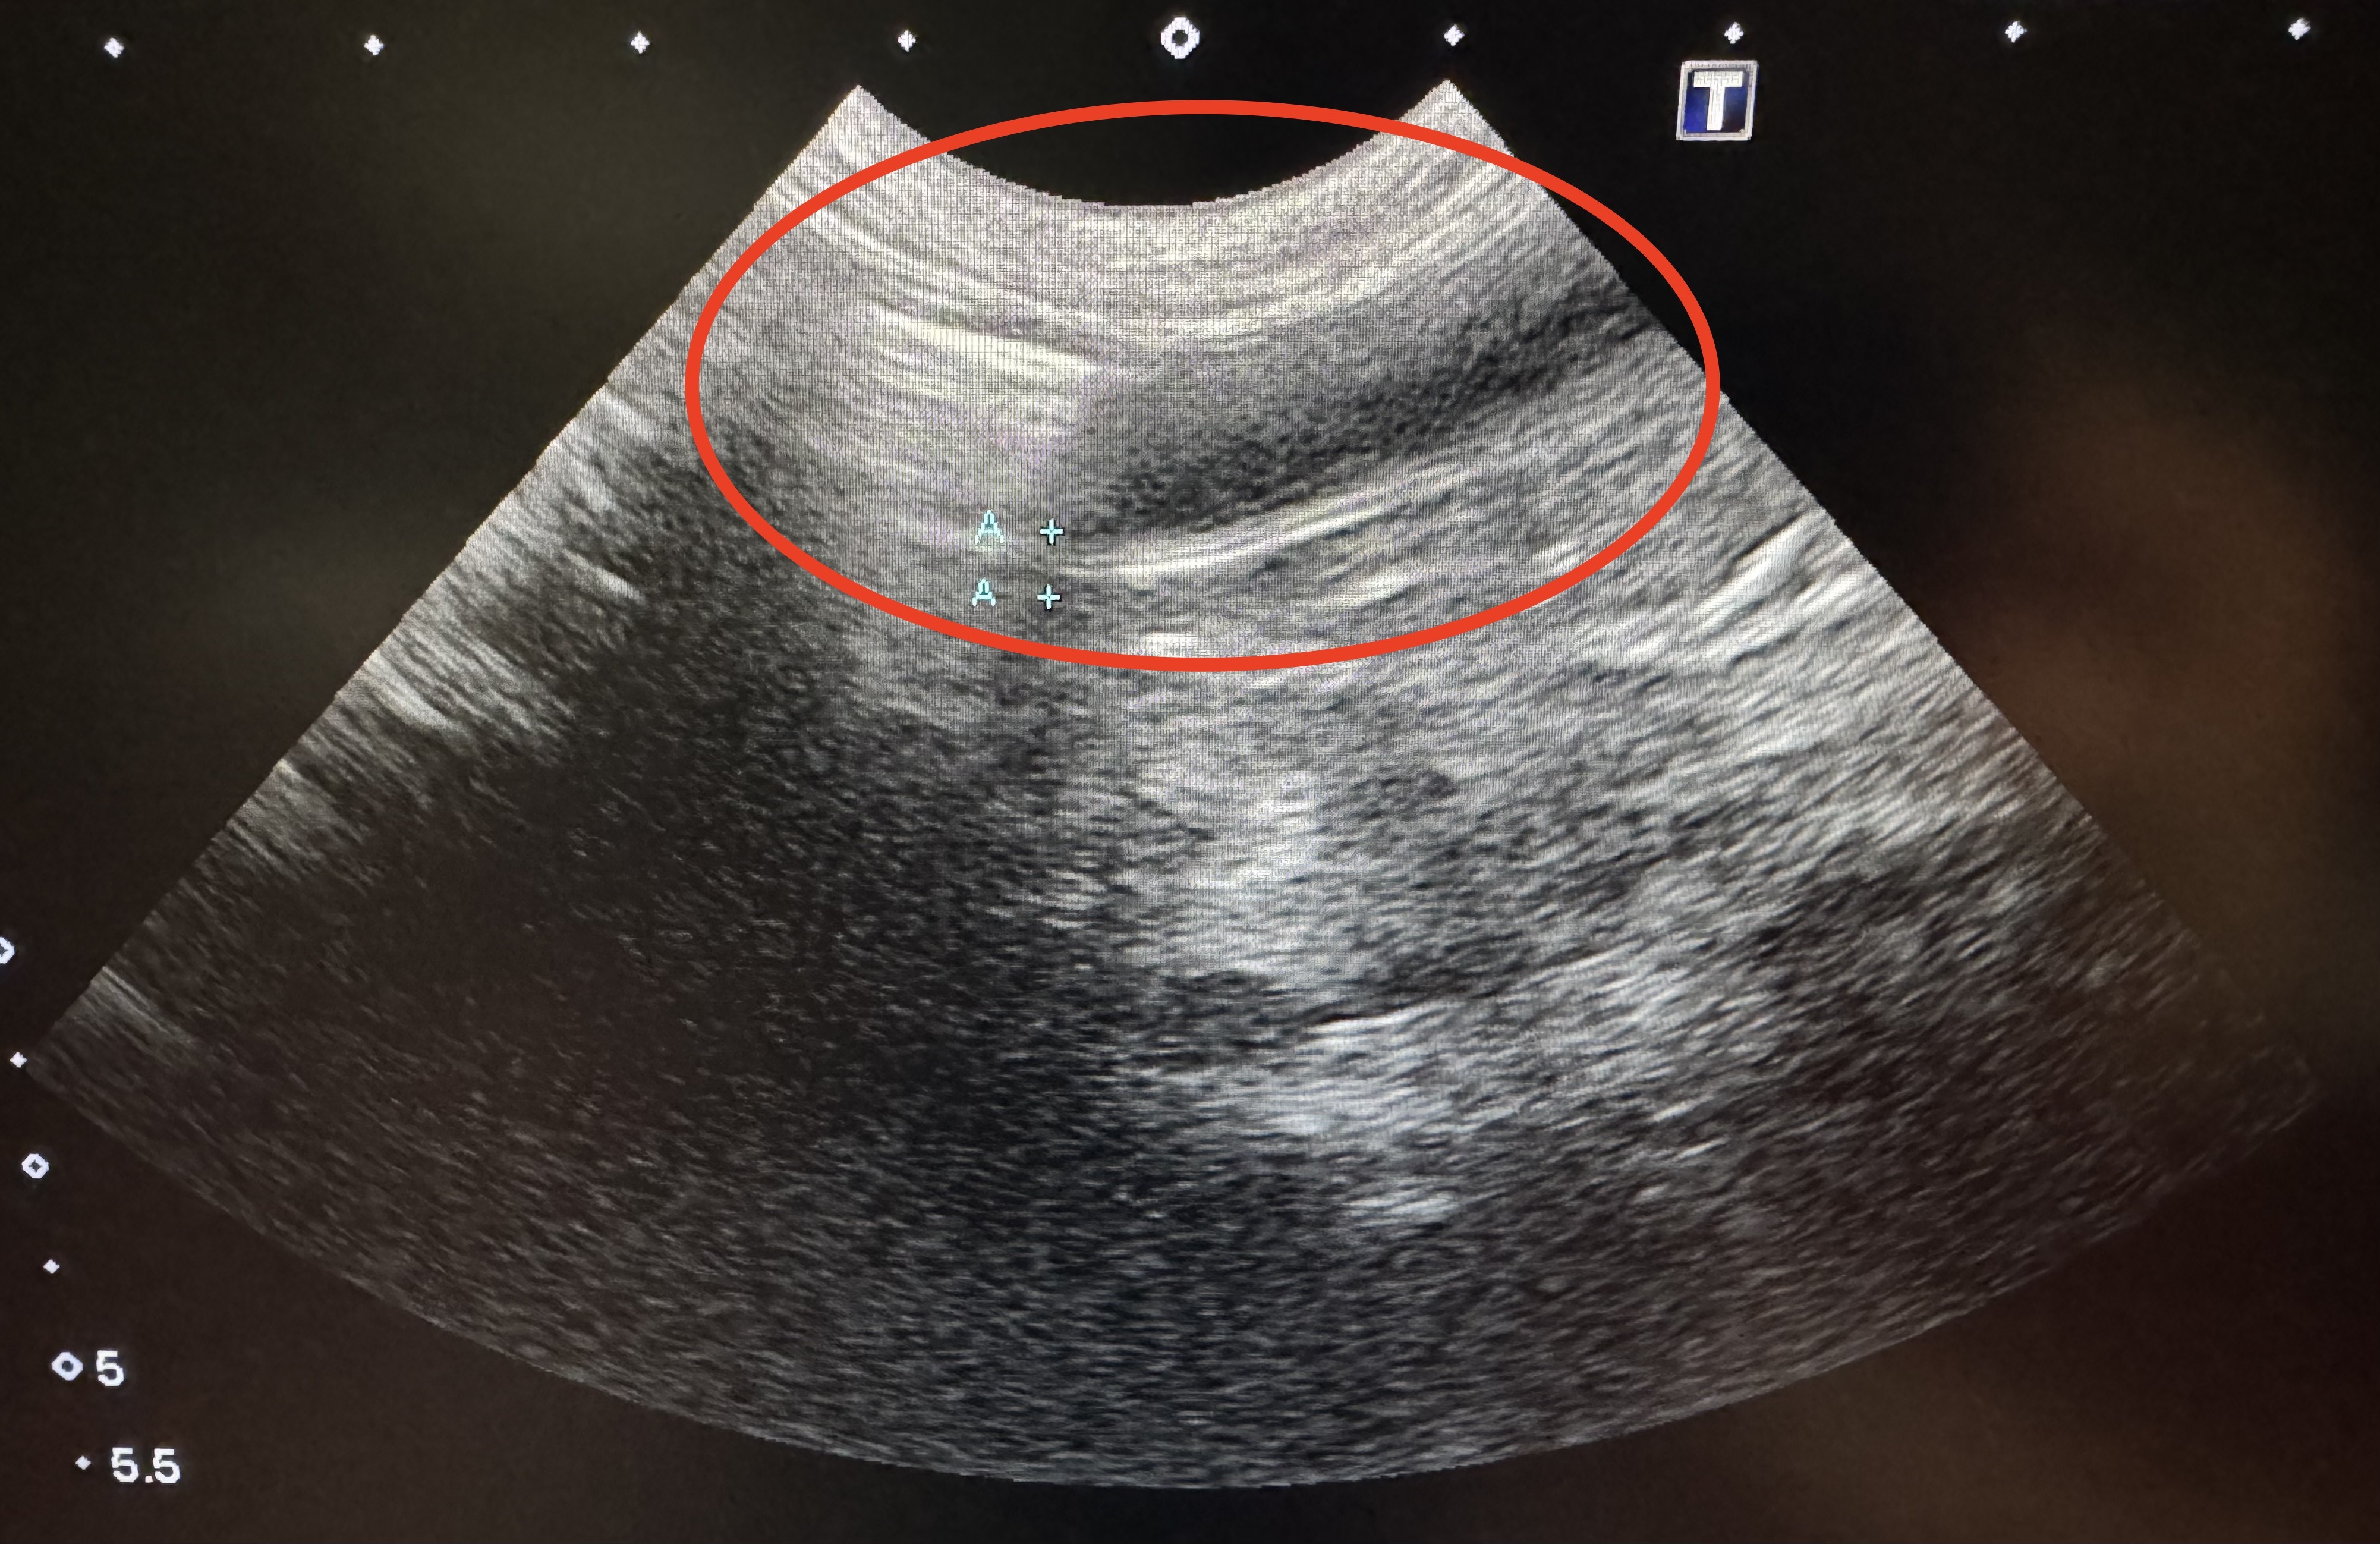

4. 超音波検査(エコー)

• 小腸の腫瘍の大きさや周囲の組織への影響を詳細に確認します。

12歳の日本猫のケースです。慢性的な体重減少(2.75Kg)で来院されました。腹部エコーを実施したところ、小腸で音響陰影(白く跳ね返る)を伴う液体貯留(黒く見えるところ)所見(写真の赤丸のところ)を認めました。これは腸の通過がうまくいかない何かしらの問題(異物で詰まっているか、小腸腫瘍などで詰まっているか)が生じている可能性があり、外科的に問題を解決する必要があります。このため、術前検査で手術の安全性を確認後、開腹手術となりました。